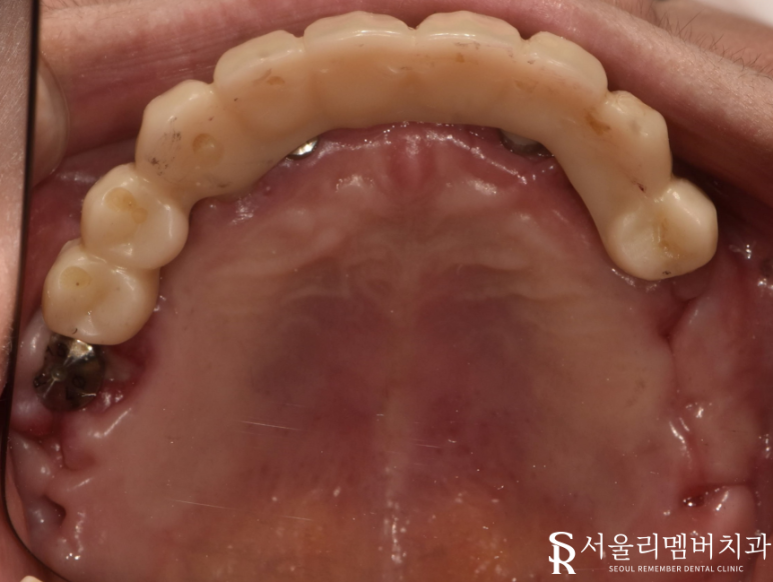

이후 생활하는 데에 불편함이 없도록 임시 보철을 올려드렸습니다.

몇 달 뒤, 최종 보철 세팅을 위해 다시 내원하셨는데요.

자 이제 결과가 어떻게 됐는지 확인을 해야겠죠?

이전에는 썩어있거나 이미 빠져버린 채 남아있던 치아들이

자연치와 유사한 외관을 자랑하는 지르코니아 크라운으로 꽉 채워져 있네요.